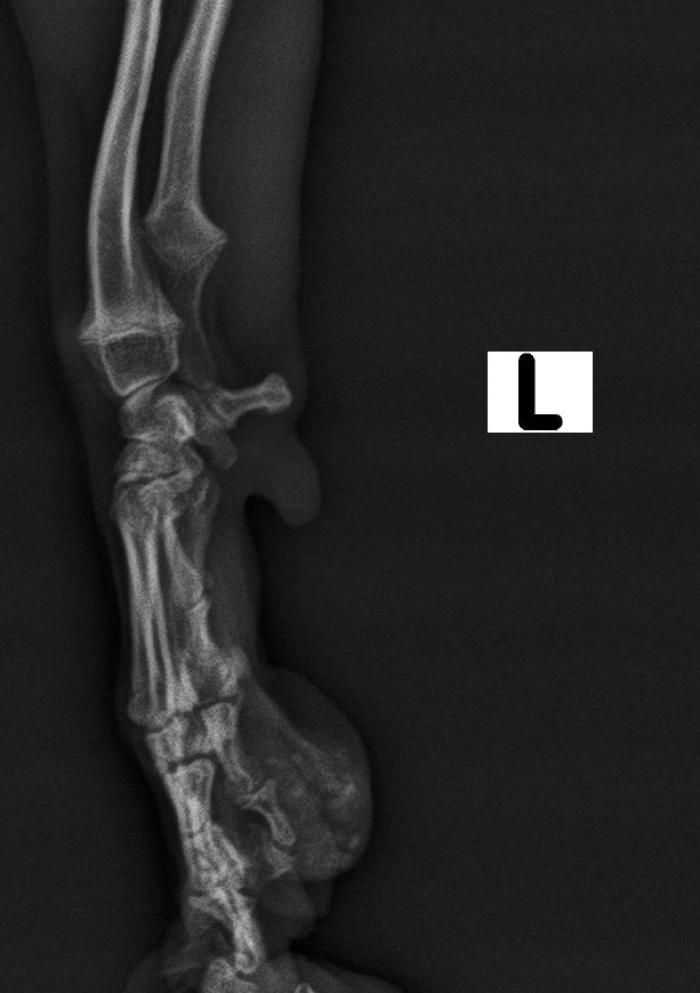

Las radiografías latero-laterales y dorso-ventrales de las extremidades anteriores mostraron material amorfo radiodenso localizado en la almohadilla afectada (Figuras2 y 3). Se realizó citología PAF (Punción con Aguja Fina), analítica sanguínea y biopsia de la zona. El análisis hematológico evidenció hiperfosfatemia leve, sin alteraciones en calcio, función renal o hepática.